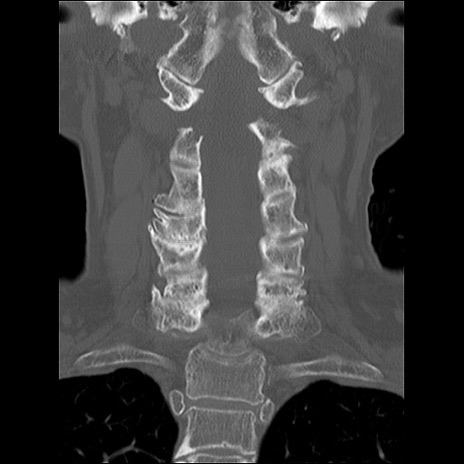

症例48 頚椎CT(冠状断像)

頚椎CT